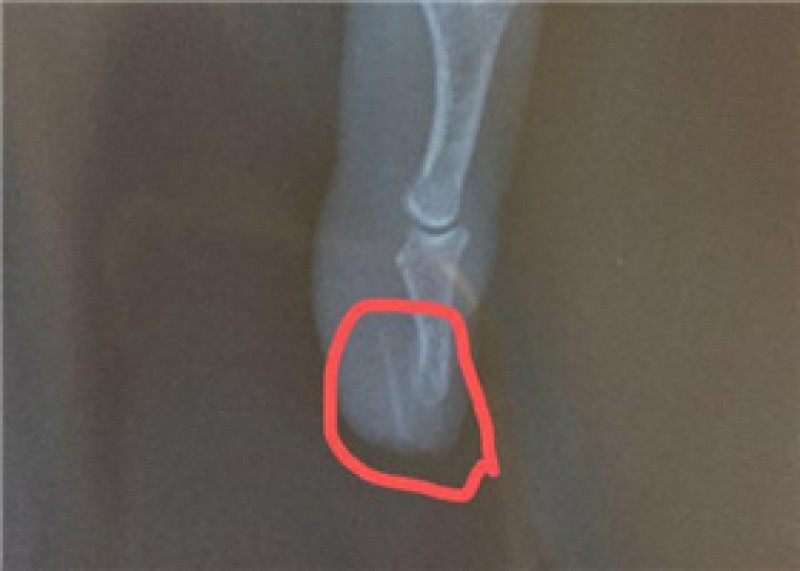

术中,医生在患者骨盆直肠窝、括约肌间取出一根长约2.6厘米、直径约0.1厘米的骨性牙签状鱼刺,原来这才是“真凶”。术后,高贵云告诉张先生,他的不适是因鱼刺所致,张先生这才恍然大悟,前几日吃过鱼误吞了鱼刺。